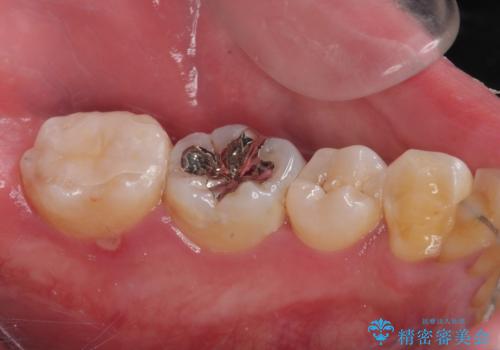

- 詰め物が欠けて虫歯になっていることを気にして来院された患者様です。以前に保険のプラスチックの治療を行われていた状況でした。

歯と歯が接しているところの虫歯のため、セラミックの詰め物(セラミックインレー)での治療を進めていくことにしました。

拡大鏡視野下で、保険のプラスチック、虫歯の除去を行い、セラミックインレーに適した形に整えました。